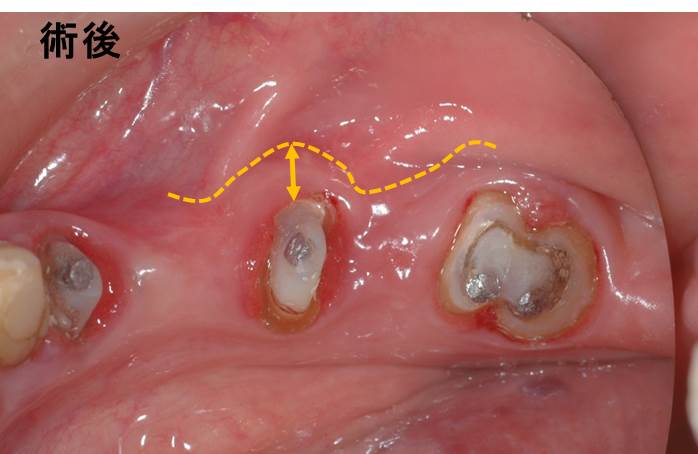

移動が終了して縫合後の写真です。移動した部分にはテルダーミスという創傷治癒材を移植しています。

歯の周囲に「動かない歯茎」が3mm程度形成されました。